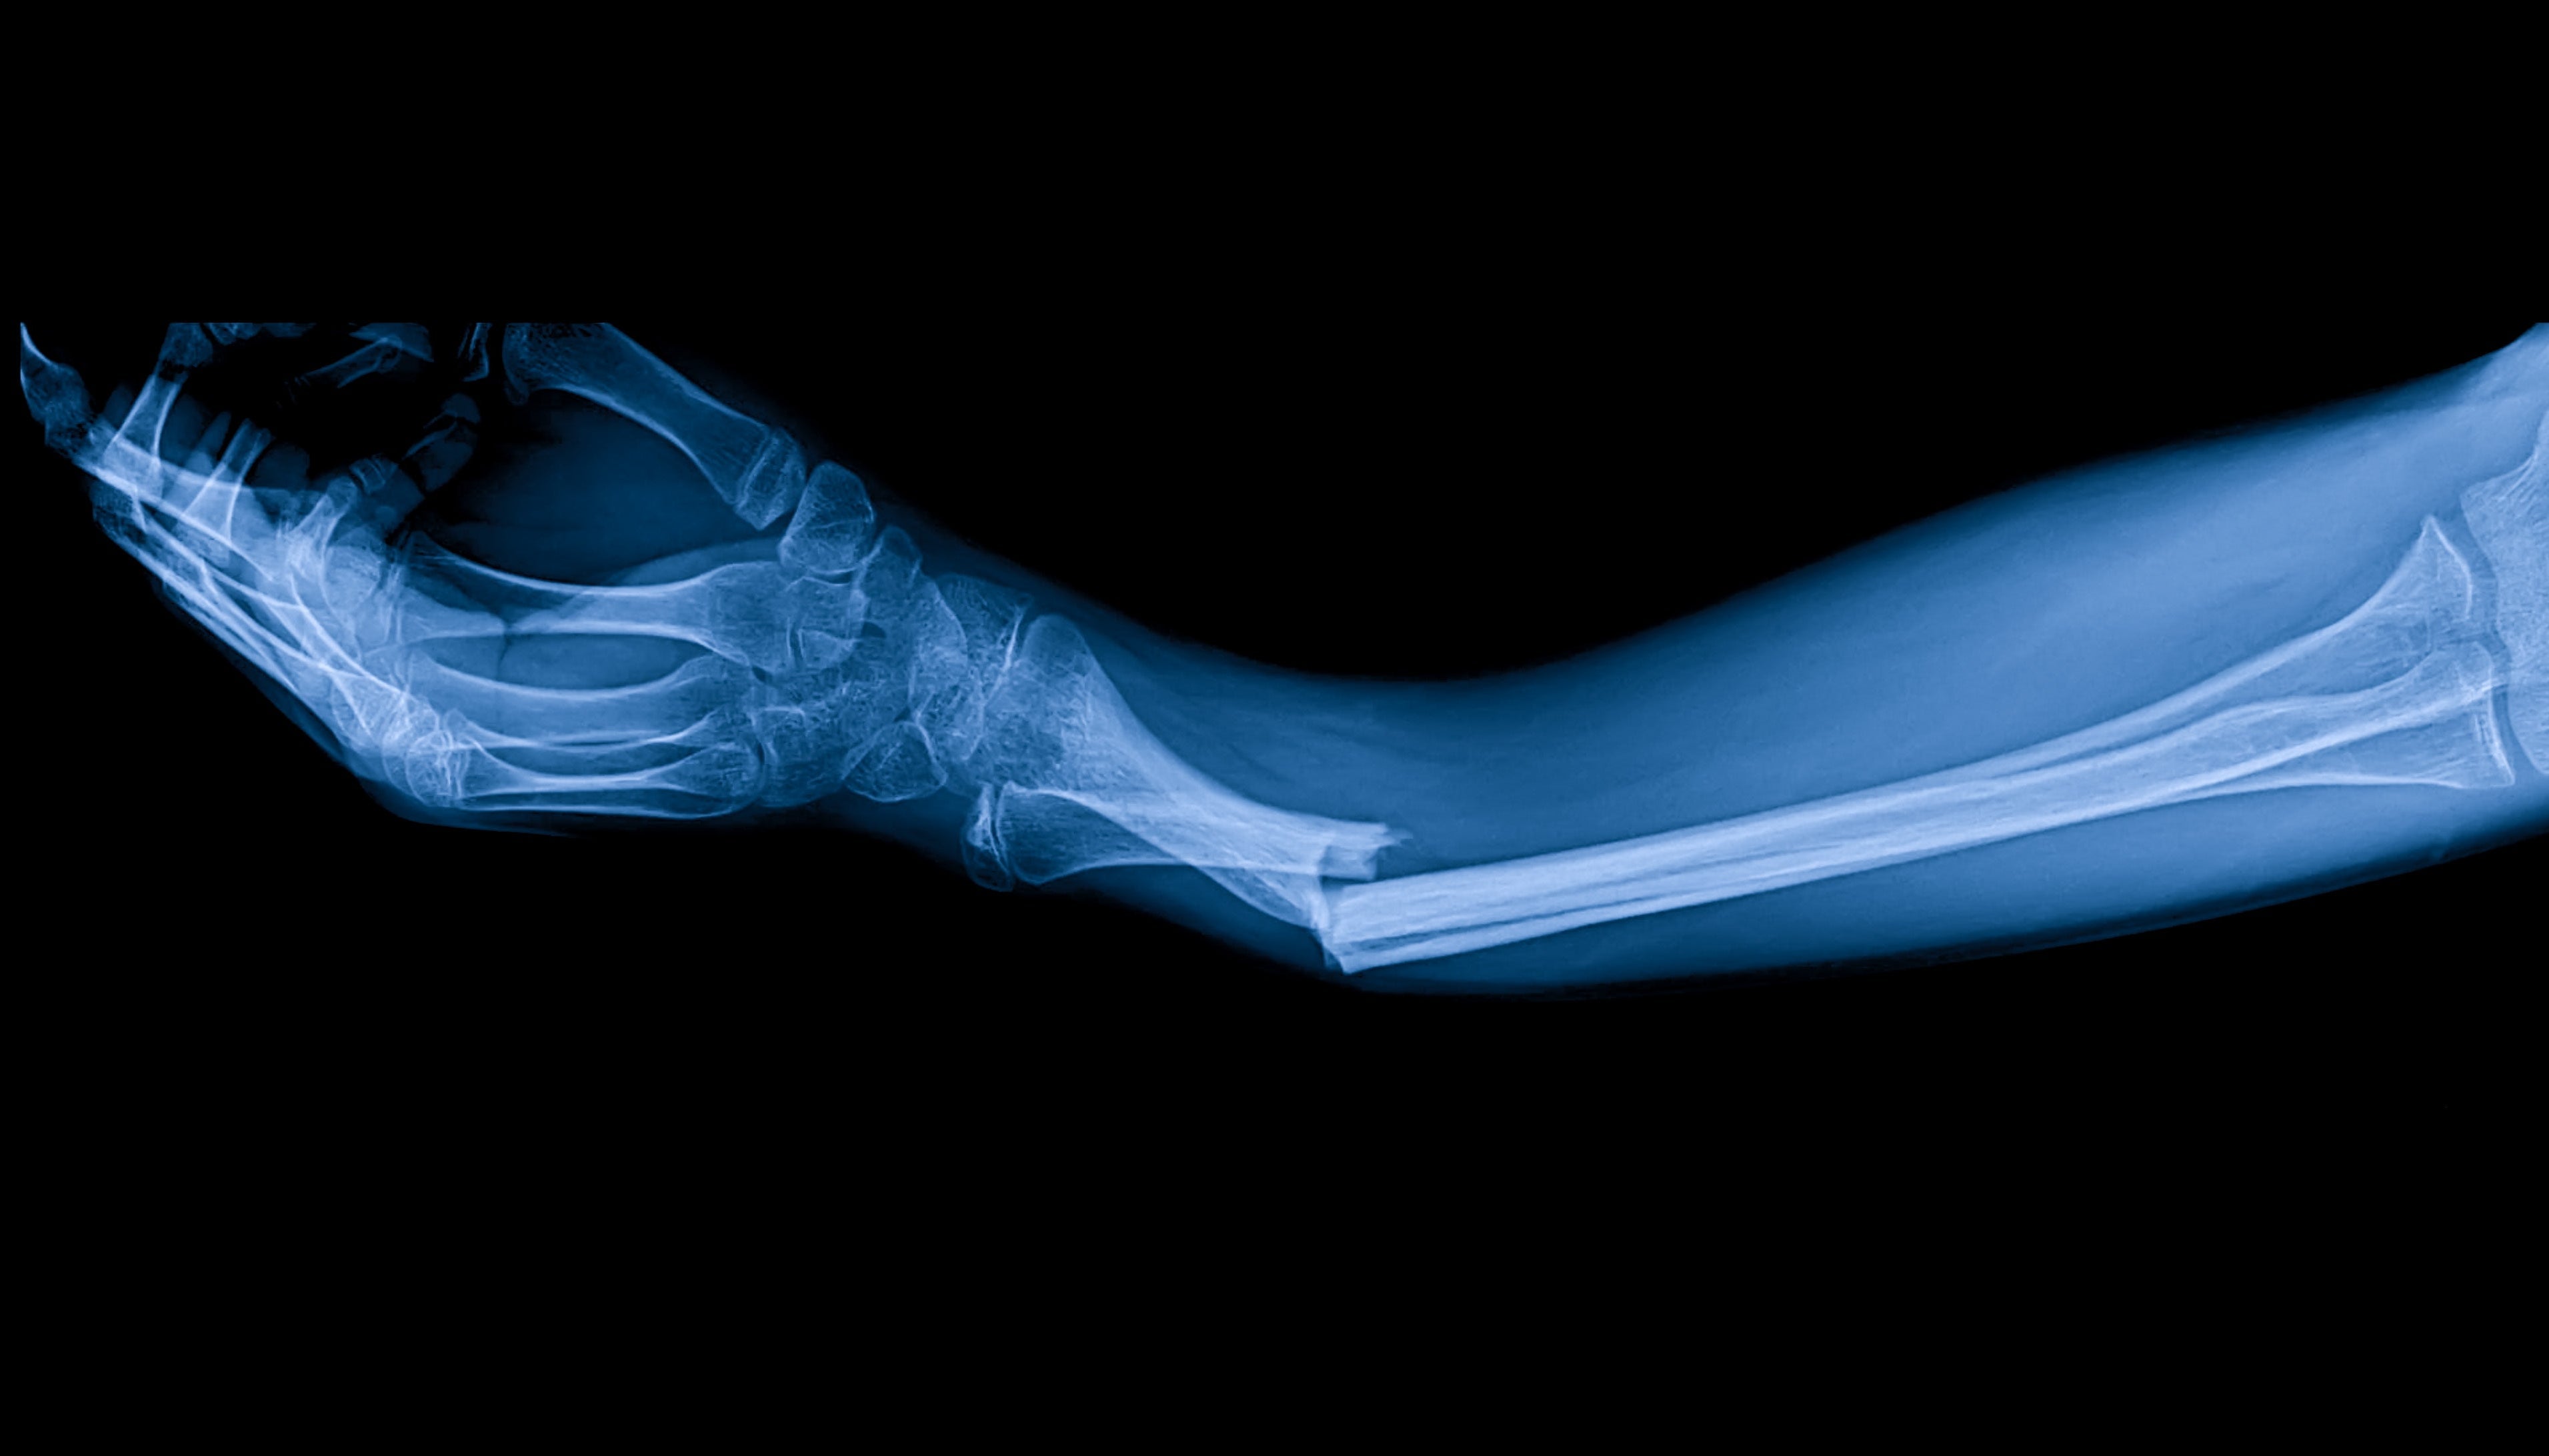

Bone fractures can result from accidents, falls, or sports injuries, requiring a significant recovery period that varies depending on the severity and location of the fracture. Traditional bone healing methods include immobilization with casts or splints, and sometimes surgical interventions. PEMF therapy complements these methods by stimulating cellular repair and bone growth at the molecular level.